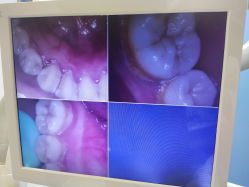

• 南京医科大学友谊整形外科医院

• 全部图片

• 全部图片»

• 效果(1030)»

• 环境(7064)»

• 其他(7)»

• 商户官方图片»